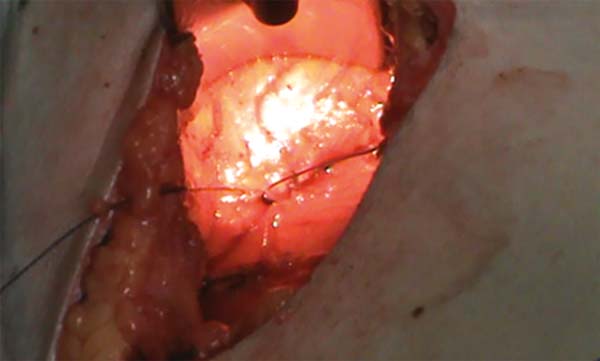

O passo seguinte é o de fixação do tecido mamário ao músculo peitoral com 9 a 12 pontos de fio absorvível 3.0 multifilamentar (Figura 1); durante este procedimento a mama é mantida sustentada no sentido vertical por 2 pontos de fio de algodão 2.0 posicionados no ápice do novo cone mamário (Figura 2). Ao final da fixação, já se nota uma pexia razoável da mama em relação ao lado não operado (Figura 3).

Este tempo cirúrgico tem por objetivo liberar amplamente o músculo (Figuras 4 e 5) e deixá-lo mais livre possível de cinta muscular na porção inferior para evitar que a prótese seja deslocada superiormente. Ressaltamos que não houve secção significativa do músculo. Como rotina não fizemos drenagem, a hemostasia nas áreas descoladas foi rigorosa e também evitamos hipotensão arterial para a maior segurança no controle da hemostasia.